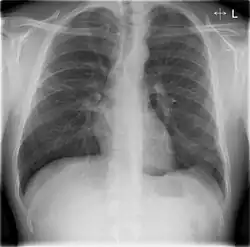

Chest X-rays and X-ray computed tomography (CT) can reveal areas of opacity (seen as white), indicating consolidation.[14] CAP does not always appear on x-rays, sometimes because the disease is in its initial stages or involves a part of the lung not clearly visible on x-ray. In some cases, chest CT can reveal pneumonia not seen on x-rays. However, congestive heart failure or other types of lung damage can mimic CAP on x-ray.[16]

When signs of pneumonia are discovered during evaluation, chest X-rays and examination of the blood and sputum for infectious microorganisms may be done to support a diagnosis of CAP. The diagnostic tools employed will depend on the severity of illness, local practices and concern about complications of the infection. All patients with CAP should have their blood oxygen monitored with pulse oximetry. In some cases, arterial blood gas analysis may be required to determine the amount of oxygen in the blood. A complete blood count (CBC) may reveal extra white blood cells, indicating infection.

The CAP outpatient mortality rate is less than one percent, with fever typically responding within the first two days of therapy, and other symptoms abating in the first week. However, X-rays may remain abnormal for at least a month. Hospitalized patients have an average mortality rate of 12 percent, with the rate rising to 40 percent for patients with bloodstream infections or those who require intensive care.[30] Factors increasing mortality are identical to those indicating hospitalization.